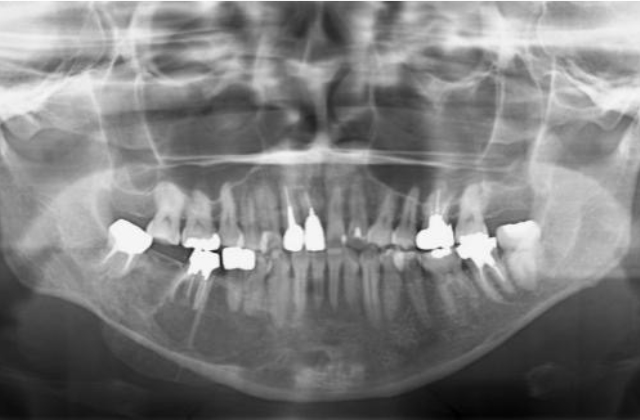

当科では、口腔内や顎骨内に発生する良性腫瘍、嚢胞性疾患に対し手術を行っています。ともに無痛性に緩慢な増大を特徴とするため、発見された際には顎骨の広範囲におよび、歯根吸収や下顎管の圧排を伴っている症例も少なくありません。特に若年者の顎骨腫瘍(嚢胞)の場合、顔貌の変形や下歯槽神経の損傷に配慮し、まず初期治療として開窓を行い、病変の縮小と骨新生を確認後に摘出を行います。ただし、エナメル上皮腫などの再発率の高い病変に対しては、一期的に顎骨切除を行うとともに、腸骨や腓骨を用いた硬組織再建を積極的に行っています。その際は術前にCT撮影を行い、3D画像によるモデルサージェリーを基にオーダーメイドのプレートを作製し、確実かつ迅速な手術を行っております。